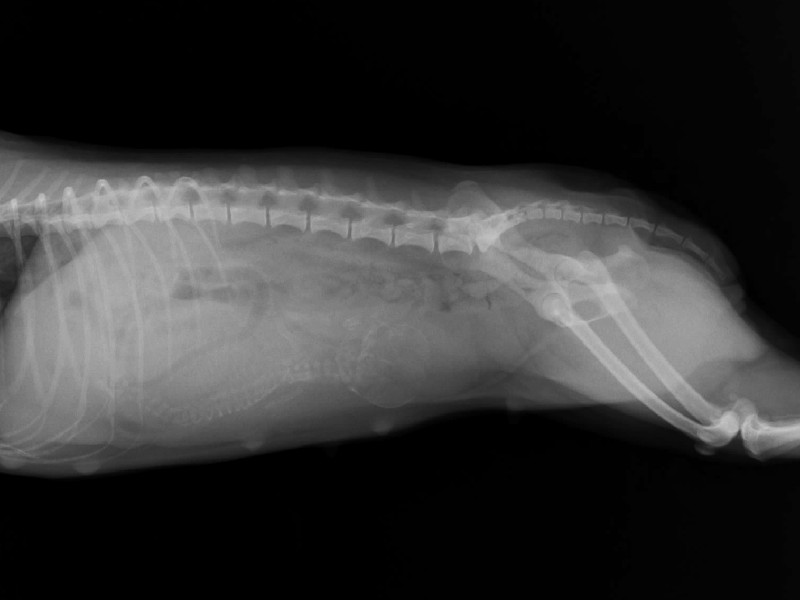

急にお腹が大きくなって、ぐるぐる鳴るようになったので、獣医さんにいってきました。

レントゲンを撮ってもらったら、良く育ってる大きくて元気な子が1わんでした。

エヴァは骨盤の産道が広いのでギリギリ自然分娩できるかも知れないけど

帝王切開になる可能性は低くないと言われてしまいました・・ ^^;)/

予定日は来週の月曜日から木曜日あたりなんだそうです。

出産の兆候として3つ教えてもらってきました。

1)食欲が極端に落ちて、まったく食べなくなる。

2)膀胱が圧迫されるので、小刻みに少量のおしっこをするようになる。

3)体温が1度ほど下がる。

メグで2度出産を経験してますけど、やっぱり心配でドキドキしてます。